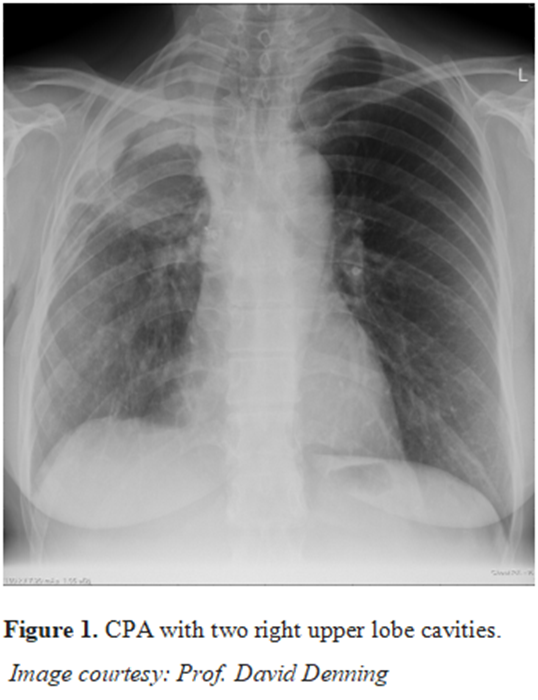

Liderado por Inderpaul Sehgal del Postgraduate Institute of Medical Education and Research, Chandigarh, este ensayo unicéntrico, prospectivo, abierto y de superioridad incluyó adultos mayores de 18 años con aspergilosis pulmonar cavitaria crónica o aspergilosis pulmonar fibrosante crónica. Los participantes fueron asignados al azar en una proporción 1:1 para recibir itraconazol o voriconazol (200 mg dos veces al día), ambos por vía oral, durante seis meses. Los criterios de valoración primario y secundario fueron la proporción de participantes que lograron una respuesta favorable a los 6 meses y los análisis de seguridad.